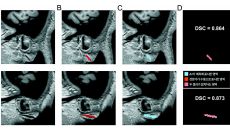

귓불의 사선 주름 ‘프랭크 징후’와 심뇌혈관질환 연관성 밝혀졌다

거울을 보다 귓불에 사선으로 깊게 파인 주름이 보인다면 주의가 필요하다. 대수롭지 않게 넘기기 쉽지만 ‘프랭크 징후(Frank- 20시간전